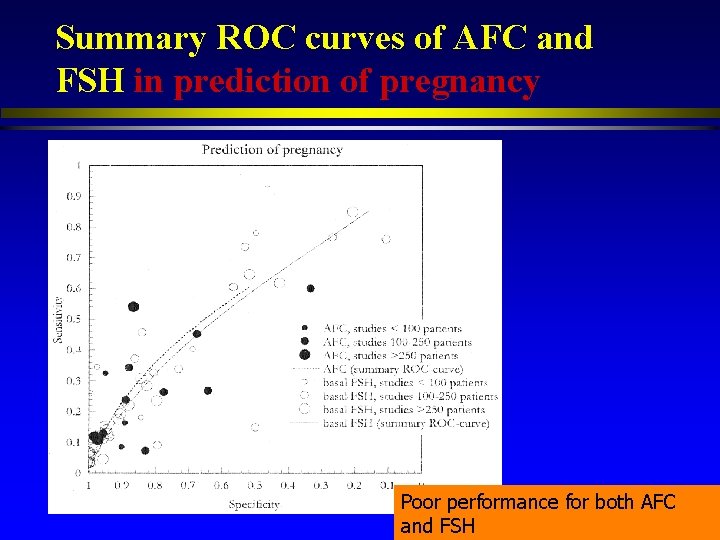

Summary ROC curves of AFC and FSH in prediction of pregnancy Poor performance for both AFC and FSH